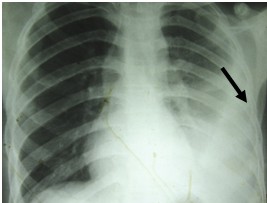

First thing you do is to get the chest x-ray done. The Consult a physician and show him the chest x-ray. If chest x-ray confirms the presence of water, get immediately the ultrasound examination of chest done. If the amount of water collected is between 400 to 500ml millilitres, this water in the chest needs evacuation through syringe-needle under ultrasound or CT- guide. Never allow evacuation of water without the guidance of ultrasound machine, otherwise problem of massive bleeding may occur sometimes.